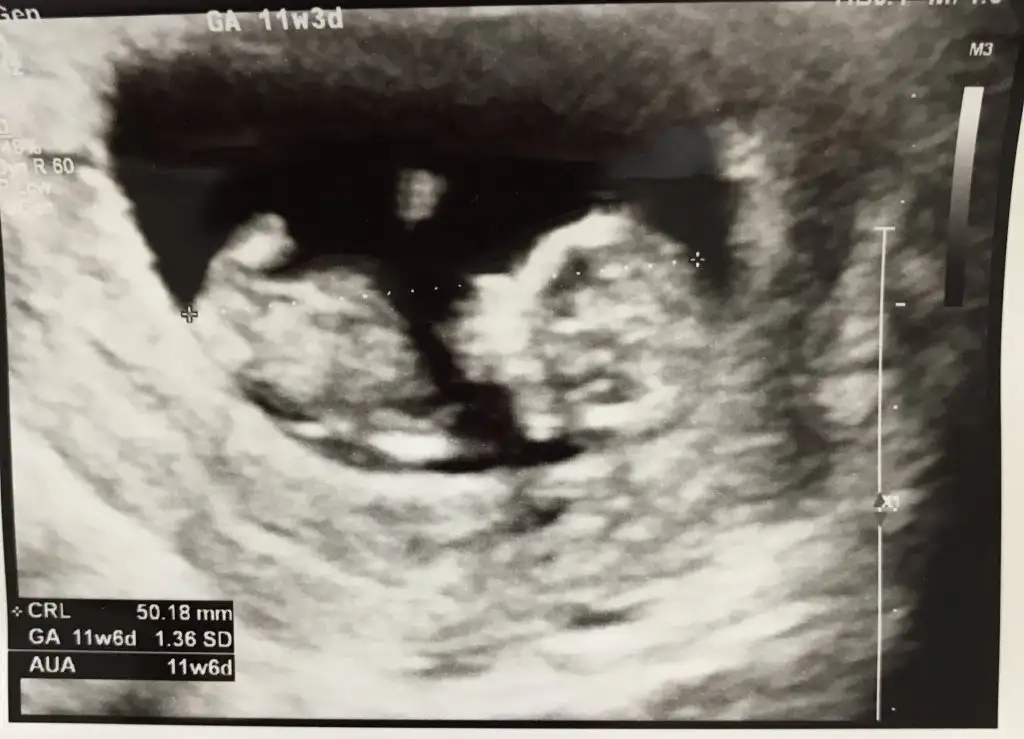

11+5 tahmini alabilir miyim:)

Canim bugun doktordan geldim Erkek dedi tahminin dogru cikti yani cokk tesekkur ederimo nasıl bir duruşpaşa gibi ama başka fotosuna da bakalim